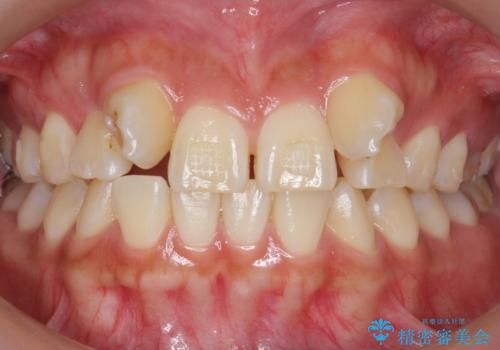

- 生まれつき上の側切歯と犬歯が逆に生えていることを主訴に来院された患者様です。

他院で矯正を行っていたそうですが、なかなか終わらないため途中で治療をやめてしまったとのことでした。

矯正以外の治療法で早く治したいとのご希望により、上顎両側犬歯を抜去しオールセラミックのブリッジによる補綴治療を行いました。